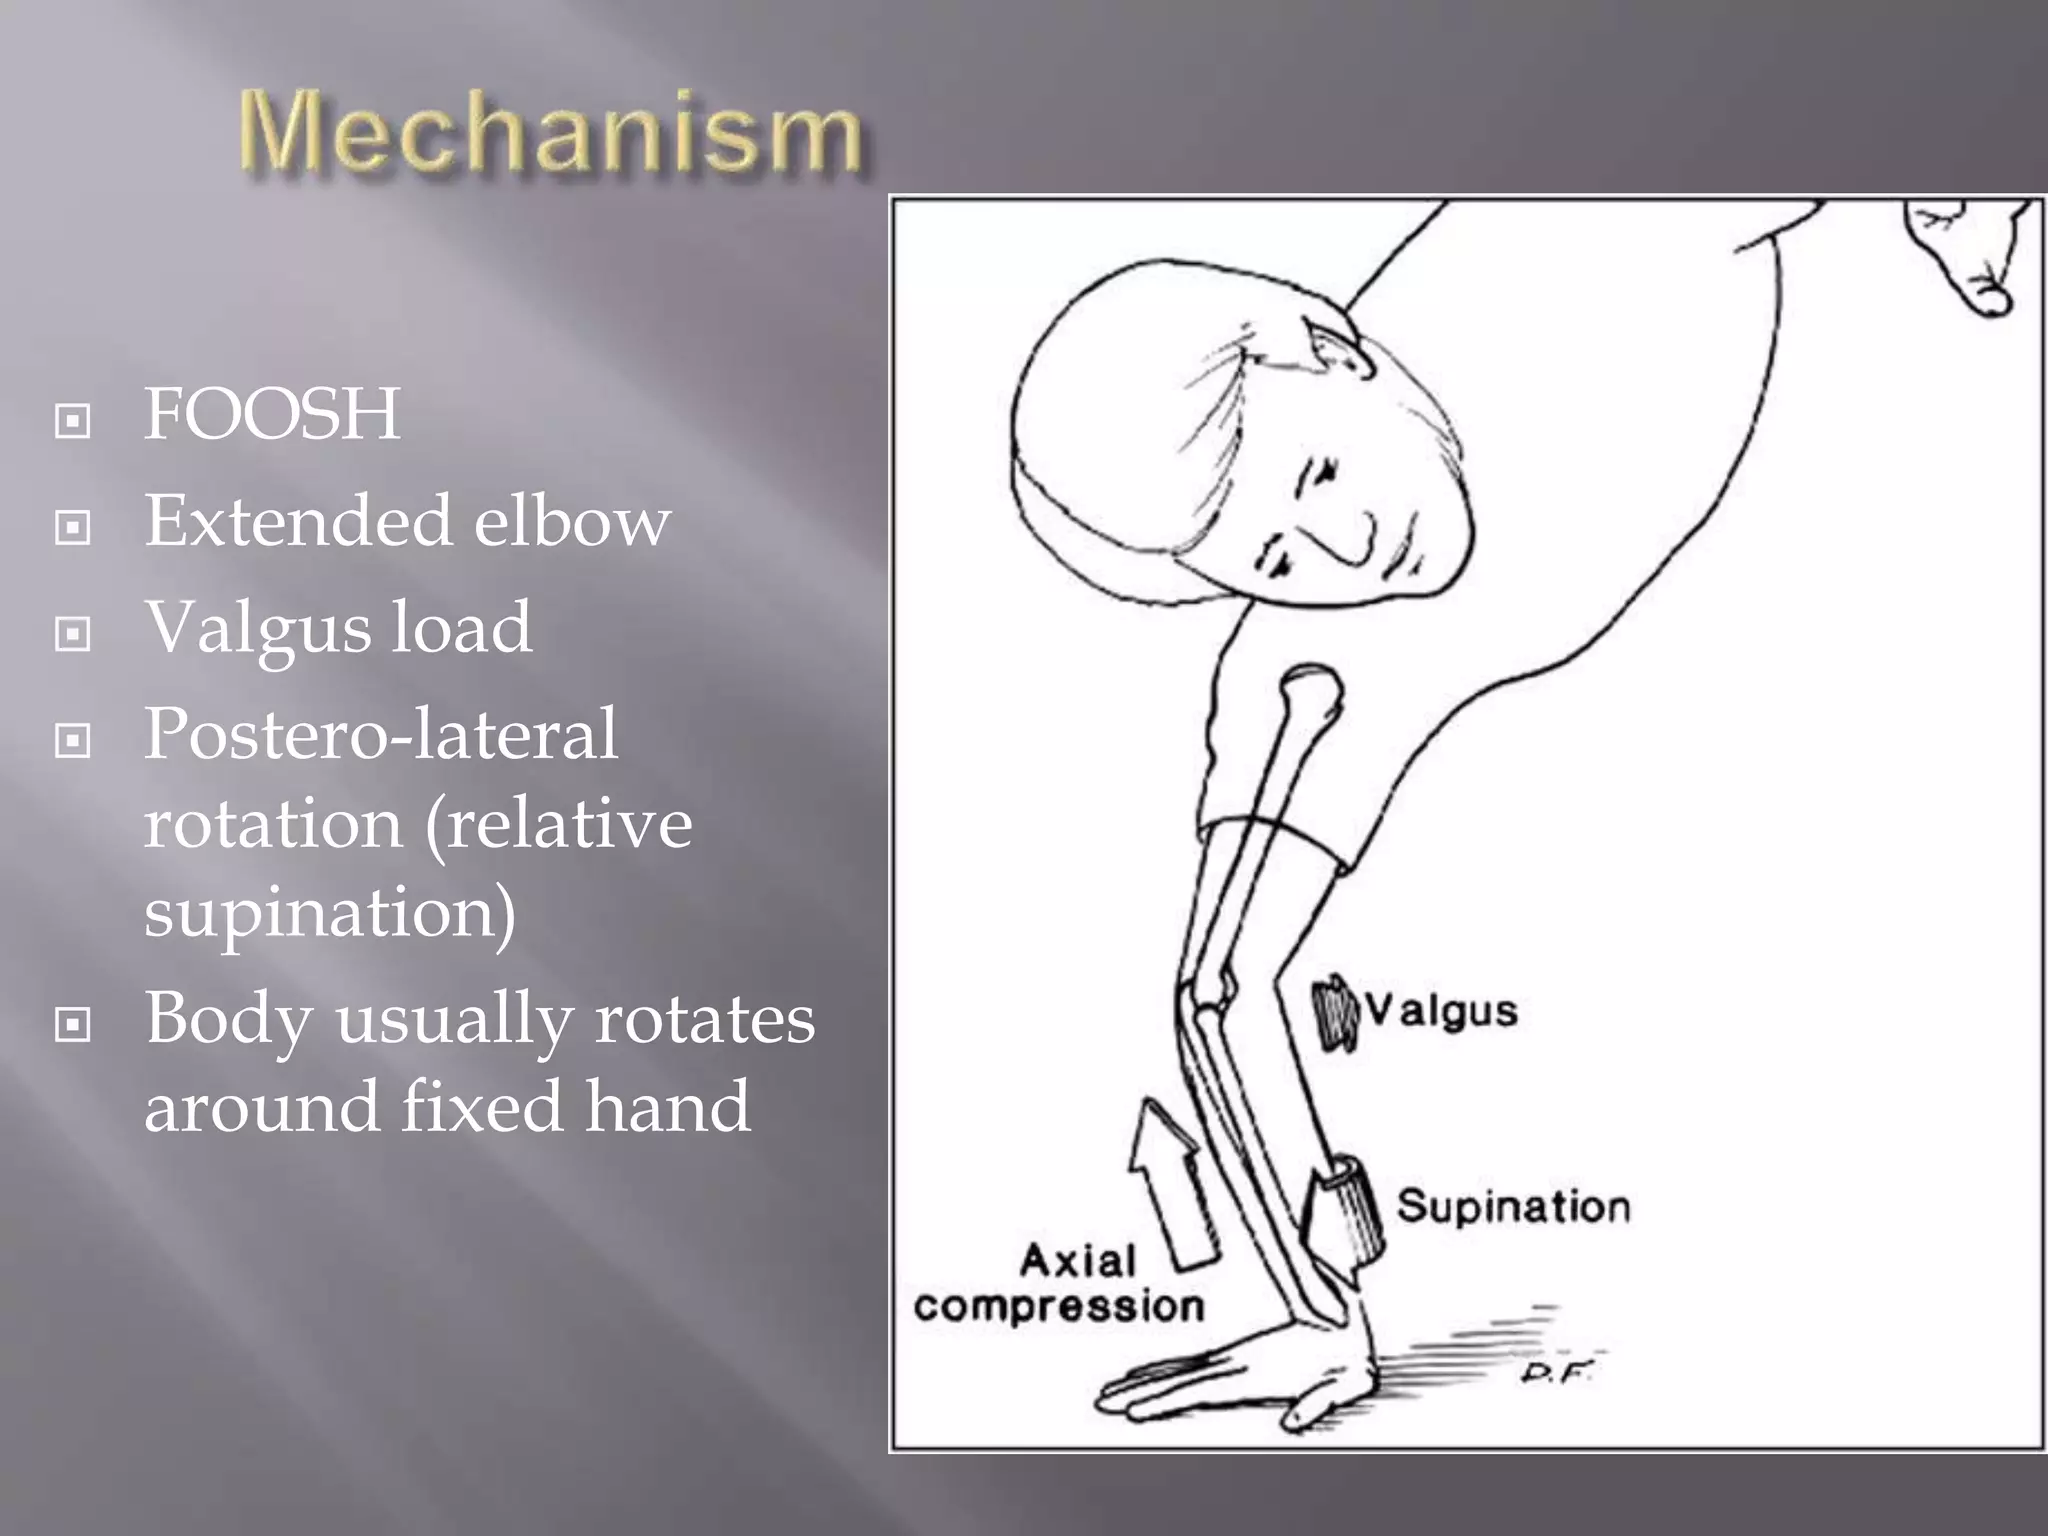

This document discusses the terrible triad injury of the elbow, which involves fractures of the radial head, coronoid process, and posterolateral dislocation. It notes the poor outcomes associated with this injury like stiffness, instability, and hardware failure. The document outlines the relevant anatomy of the medial collateral ligament and lateral uncular collateral ligament. It describes the mechanism of injury, known as the fall on an outstretched hand, and how the ligaments and capsule fail in this injury. Diagnostic imaging and classification of radial head and coronoid fractures are covered. Treatment options including observation, resection, open reduction internal fixation, and replacement are presented. Surgical approaches and techniques are also outlined.